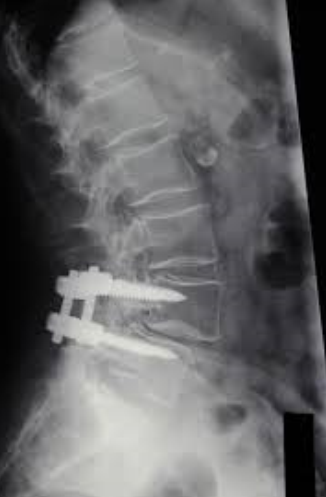

이 사건의 의뢰인은 상대방이 동석한 교통사고 피해자로서 사고 후 요통으로 ○○병원 응급실에 내원하였고 “제2요추폐쇄증후군” 진단을 받았다. 방사선 검사에서 “압박 골절”이 나타났습니다. 부상 초기에 척추의 추가 기형이 진행되거나 신경학적 증상이 나타나면 수술을 준비하고 며칠 동안 경과를 지켜보십시오. 다행스럽게도 통증은 신경학적 증상 없이 차차 가라앉았고, 정형외과를 통한 보존적 치료만이 상당 기간 지속되다가 치료가 종료되었다.